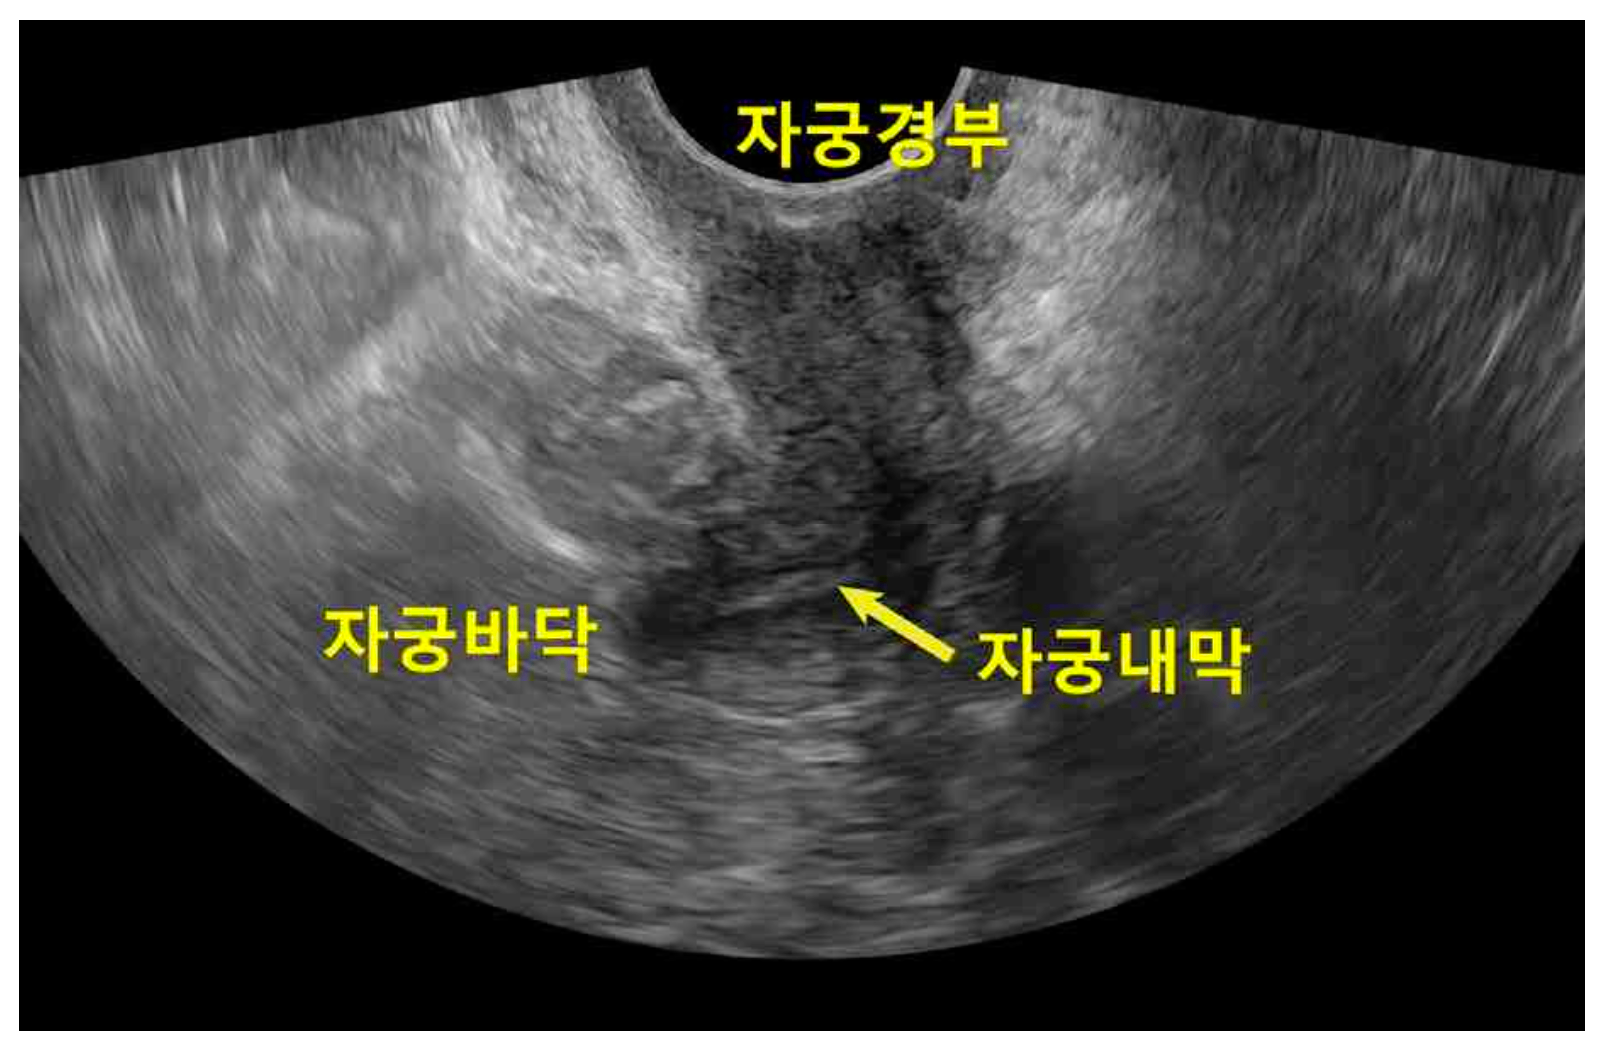

26세 산과력 0-0-0-0인 여자가 1년 전부터 월경이 없어서 병원에 왔다. 18개월 전 급성백혈병으로 진단받고 조혈모 세포를 이식받았다. 골반초음파검사 사진이다. 검사 결과는 다음과 같다. 치료는?

US: Normal uterus